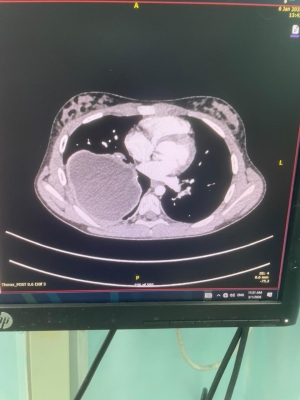

إنجاز طبي بالخدمات الطبية: استئصال أكياس رئوية لطفلتين بالمنظار لأول مرة

أجرى فريق طبي متخصص من قسم جراحة الأطفال في مستشفى الملكة رانيا العبدالله للأطفال، برئاسة العقيد الطبيب وسيم المفلح، عمليتين جراحيتين لطفلتين كانتا تعانيان من وجود أكياس كلبيّة على الرئتين، بإستخدام المنظار الجراحي دون الحاجة إلى إجراء الجراحة التقليدية، من خلال ثقوب صغيرة في الصدر. وتُعد هذه العملية الأولى من نوعها على مستوى الخدمات الطبية الملكية.

وقال مستشار جراحة الأطفال العقيد الطبيب وسيم المفلح إن إستخدام المنظار الجراحي في مثل هذه الحالات لدى الأطفال يُعد تطوراً نوعياً ومميزاً على مستوى قسم جراحة الأطفال، لما يحققه من نتائج علاجية أفضل ويسهم في تقليل فترة الشفاء، والابتعاد عن الجراحة التقليدية وما قد يرافقها من مضاعفات، مشيراً إلى أن قسم جراحة الأطفال يسعى باستمرار إلى تطوير إستخدام تقنيات المنظار الجراحي في مختلف الحالات لمواكبة التطور الطبي في جراحة الأطفال والمسالك البولية للأطفال على مستوى المنطقة والعالم.